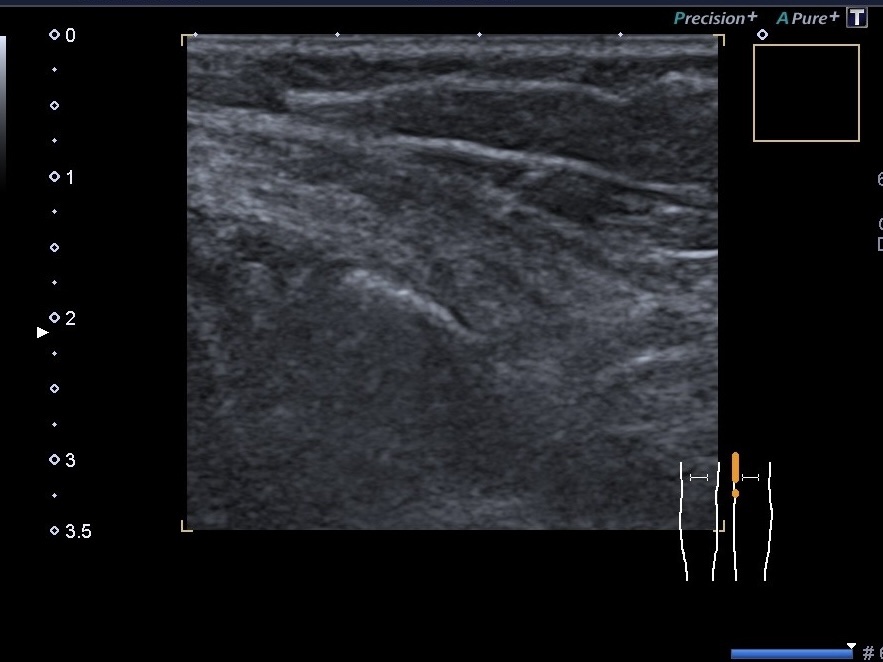

УЗД нервів при травмах. Патологія периферичних нервів може бути розділена на дві великі групи: травматичні та нетравматичні ушкодження. Травматичні ушкодження...

В нашому кабінеті УЗД Medicine Group проводять багато видів УЗД, але можливо не всі чули про УЗД нервів .Це дослідження досить не...

УЗД нервів та м’яких тканин. Якщо Ви думаєте, що дослідження нервів та м’яких тканин легко, то хочемо Вас розчарувати. Щоб...